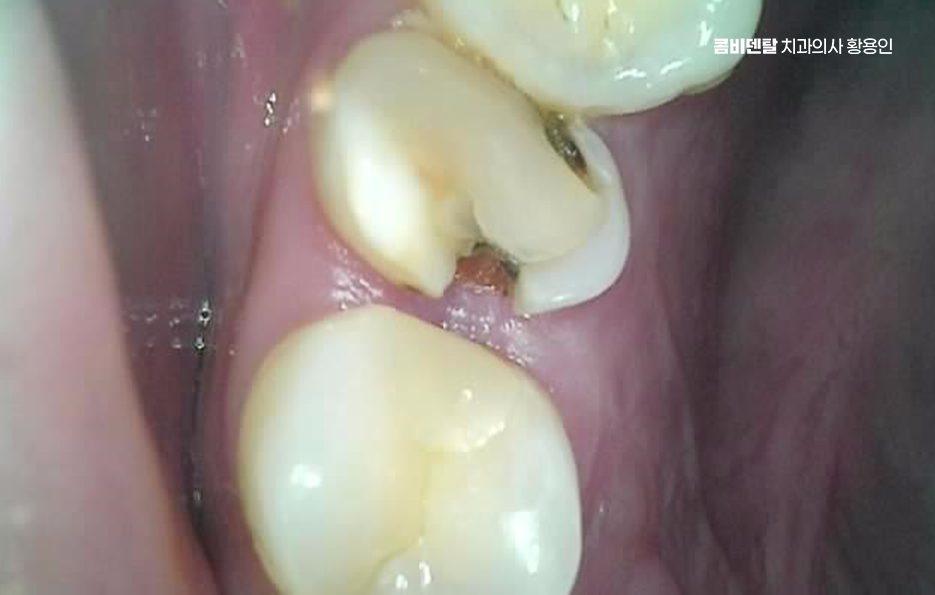

문제는 여기서 끝나지 않고 누운 사랑니와 앞 어금니 사이에 충치가 동시에 생기는 경우는 치료가 더 복잡해질 수 밖에 없는데 왜냐면 사랑니가 옆으로 누워 있으니까 앞 어금니 뒷면에 생긴 충치를 제대로 보기도 어렵고, 치료 기구가 들어갈 공간도 부족해져서 충치 치료가 더 까다로워지는 것이며 특히 앞 어금니 뒷면에 생긴 충치는 환자도 자각하기 어렵고, 진단 시기도 늦어지는 경우가 많아서 이미 신경까지 손상됐거나 신경치료가 필요한 상태로 발견되는 일도 많이 있었어요

사랑니 발치 후 충치 치료 이런 경우, 사랑니를 발치하지 않은 채로 어금니 충치 치료만 한다면 문제는 해결되지도 않고 사실상 치료적 접근도 어렵기 때문에 사랑니가 원인이 되어 어금니 충치가 생겼다면, 먼저 사랑니를 발치하고 나서 어금니를 치료하는 순서가 맞는 거예요.

또 하나 중요한 점은, 사랑니를 발치한 후 생긴 공간이 오히려 어금니 충치 치료를 더 수월하게 만들어 준다는 점으로 사랑니가 있을 때는 치료 기구 접근이 힘들었지만, 발치 후에는 시야가 확보되면서 어금니 치료가 더 깔끔하고 정확하게 가능해질 수 있어요